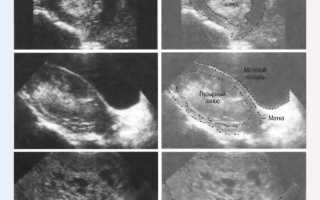

При ультразвуковом исследовании невозможно обнаружить плодное яйцо; вместо этого на экране наблюдается картина, известная как «снежная буря».